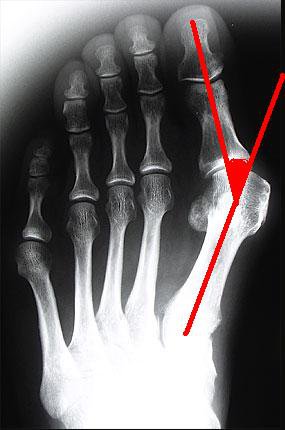

病徵及診斷:

患者拇趾呈外傾及旋轉變形。而第一蹠骨的頭部向內突出。從而發生擠壓、產生發炎。如拇趾外傾嚴重,還會重疊在二趾上或下,影響外觀及令患者疼痛。

臨床檢查後,骨科醫生會為病人照腳部X光片(要病人站著照的方為正確)。正常拇趾外翻角度應少於15度;患上此症拇趾外翻角度則超過15度。此外,醫生還會從X光片,量度其他角度以確定嚴重性並決定診治方法。